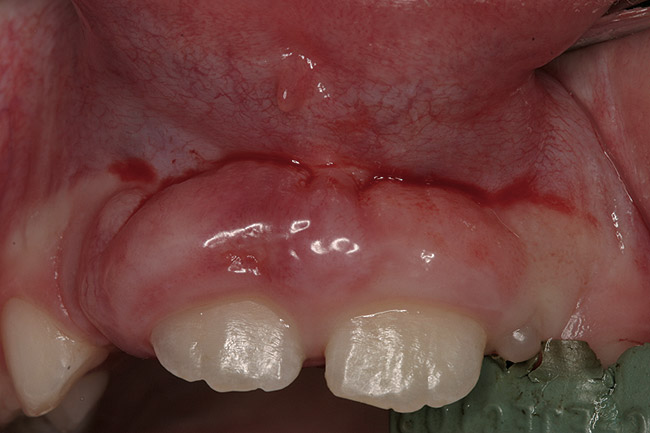

Finally, it must be noted that the psychological and emotional impact of gingival overgrowth receives no or little attention. As increasing numbers of pediatric patients are affected by systemic disease-associated gingival overgrowth, concern should be shown for how pediatric patients interpret what is happening to them and how affected children manage difficulties associated with facial appearance (Figure 1, Figure 2, Figure 3 and Figure 4).

Figure 1  Heart transplant-associated gingival enlargement in a 16-year-old girl. Frontal view.

Figure 1

Figure 2  Heart transplant-associated gingival enlargement in a 16-year-old girl. Palatal view.

Figure 2

In patients undergoing immunosuppressive therapy, the prevalence of cyclosporine-associated gingival overgrowth has been found to vary from 25% to 81%.14 In pediatric patients receiving cyclosporine A for more than 3 months, the incidence of disfiguring gingival overgrowth can approach 70%.15 Gingival overgrowth, particularly around maxillary central incisors, is common in transplant patients and the overgrowth can displace maxillary incisors and destroy anterior papillae. The damage results in extensive treatment needs and presents a challenge to traditional therapeutic periodontal approaches. A further concern is the ability of viruses, such as human cytomegalovirus, to replicate in the pockets developed from the excessive gingiva. The author and his colleagues16 detected 68.4% gingival overgrowth in adult renal transplant patients and provided evidence for a link between cytomegalovirus, gingival overgrowth, and renal transplant complications.

Facial differences can bring stigma upon children and adolescents, affect their psychosocial development, self-esteem, and quality of life.35 Because of the centrality of the face, the mouth, and a smile in human interactions, the effect of gingival overgrowth on the smiles of thousands of children cannot be minimized. Regrettably, the media and public culture place a huge value on physical appearance, which can result in a lack of opportunity for and acceptance of those who look different.36 Reports of perception of physical appearance and social alienation suggest that children with facial differences undergo serious psychological and emotional problems as a result of the feelings of isolation and powerlessness.37 Because gingival overgrowth is a visible facial feature it can be categorized as a facial difference. Therefore, by extrapolation, the studies cited35-37 support that human relationships and interaction are negatively influenced by the appearance of gingival overgrowth. Life can be only the sum of moments, and moments lost to pain and suffering that are psychological or social in nature can mean as much or more than moments lost to physical pain and suffering.